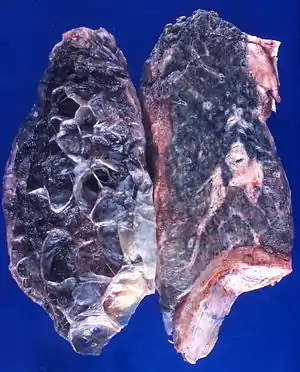

| Left lung completely affected by bullae shown in contrast to a normal lung on the right. | |

| Causes | Tobacco smoking, pollutants |

In the lungs, emphysema involves enlargement of the distal airspaces,[2] and is a major feature of chronic obstructive pulmonary disease (COPD). Other pneumatoses in the lungs are focal (localized) blebs and bullae, pulmonary cysts and cavities.